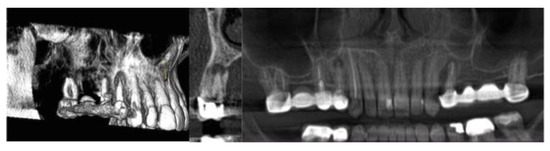

| 1 | 46 | Female | Apical Granuloma |

| 2 | 31 | Female | Periapical Cyst |

| 3 | 56 | Male | Apical Granuloma |

| 4 | 49 | Male | Apical Granuloma |

| 5 | 27 | Male | Periapical Cyst |

| 6 | 52 | Female | Periapical Cyst |

| 7 | 48 | Male | Apical Granuloma |

| 8 | 61 | Male | Periapical Cyst |

| 9 | 43 | Female | Apical Granuloma |

| 10 | 39 | Male | Apical Granuloma |